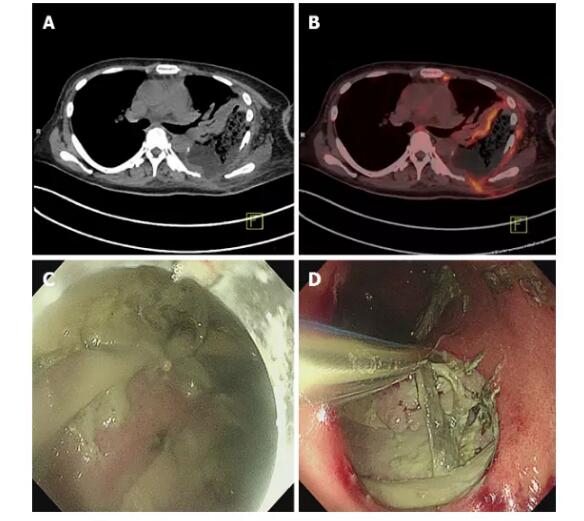

体检 该患者于2019年7月31日再次入院时,脸色苍白且脱水,身体左胸壁伤口重新张开,约2厘米×3厘米,并散发着恶臭化脓性分泌物。 实验室检查 2019年8月8日对胸膜引流液进行细菌培养和药物敏感性测试,结果显示耐甲氧西林的金黄色葡萄球菌和白色念珠菌呈阳性。定期对胸膜脓肿引流液进行细菌培养,表明存在铜绿假单胞菌(8月29日)和小肠克雷伯菌(9月30日)。 影像检查 当患者于2019年5月就诊时,全身正电子发射断层显像(PET-CT)显示形成了胃胸瘘,病变累及外侧胸壁(图3A和B),左肺活动性恶性肿瘤,下节段胸骨切开术,以及肝右叶。在内窥镜检查中确认到位于胃大曲率处的约5 cm的胃胸瘘(图3C和D)。2019年9月在计算机断层扫描(CT)检查中检测到所应用的引流管引流的脓肿不良。

然后患者接受2个月的充分引流并用三氧水冲洗。 结果与随访 病人的感染得到了令人满意的控制,胸腔闭式引流后白细胞数量和中性粒细胞比例逐渐降低(图4A和B)。降钙素原也下降,表明相关症状,包括严重的细菌感染和败血症,正在逐渐改善(图4C)。C反应蛋白水平波动,与患者潜在疾病的变化有关,包括阻塞性肺炎(图4D)。 治疗期间的CT检查显示,胃胸瘘壁逐渐增厚(图5A-F)。使用Interactive Medical Image Control System 21软件(比利时Materialise)从CT图像重建瘘管的三维立体图。使用ITK-SNAP 3.8.0(宾夕法尼亚大学的尤什科维奇和犹他大学的Gerig),基于瘘管的体素体积的总和来测量瘘管体积,分别为131、144、155、162、98和131。在8月20日,8月26日,8月30日,9月2日,9月17日和10月8日分别为96 mL(图5A’-F’)。